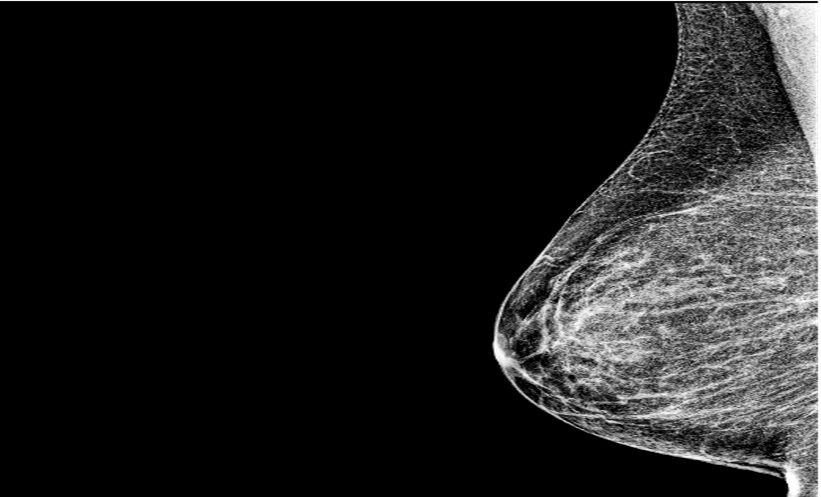

CEM combines conventional mammography with contrast enhancement to improve visualisation of tumour vascularity. In breast cancer imaging, accurate estimation of tumour size and spread is essential to guide surgical planning and detect multifocal or multicentric disease.

The study included 52 women with biopsy-confirmed breast cancer who underwent both CEM and MRI. Two radiologists independently reviewed imaging studies at separate times and were blinded to pathology outcomes, reducing recall bias.

CEM identified 51 of the 52 primary tumours, while MRI detected all cases.

Tumour size measurements were very similar between the two imaging methods. The average size was 24.9 mm on CEM and 25.2 mm on MRI. The high intraclass correlation coefficient (0.975) indicates that strong agreement between the two techniques.

When compared with post-operative histopathology, CEM’s assessment of total disease extent matched exactly on average, with both reporting a mean of 32.6 mm. MRI, in contrast, slightly overestimated disease extent, with a mean measurement of 35.0 mm.

Larger differences of more than 20 mm were seen in five patients, mainly in cases involving non-mass enhancement, where imaging interpretation can be more challenging.